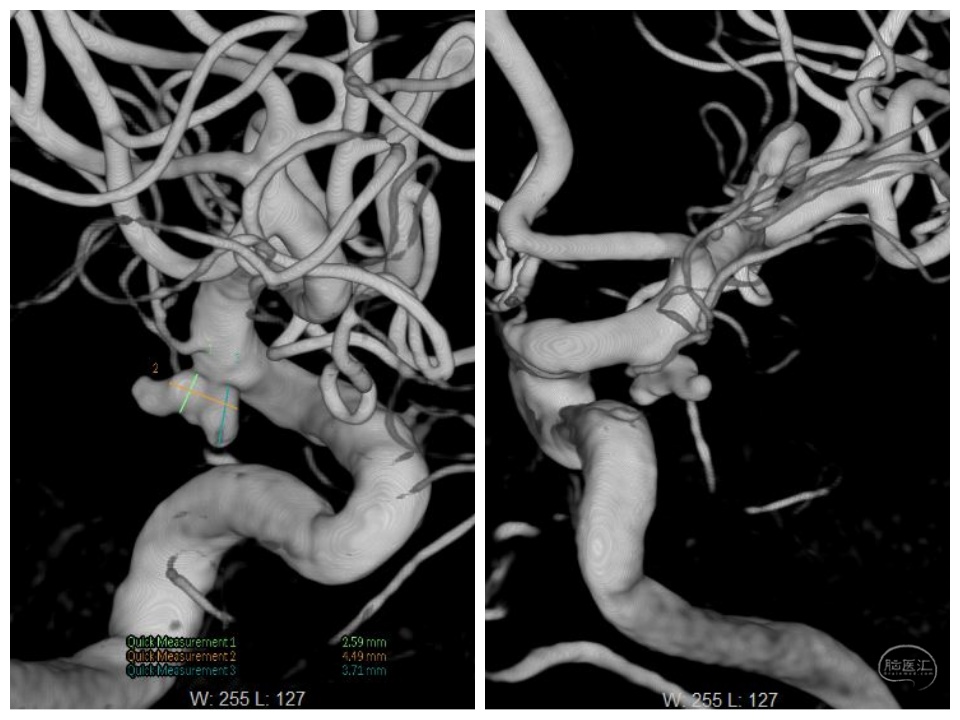

术后工作位造影

换角度观察,栓塞满意。

正位

术后第二天CT:未见异常,术后一周顺利出院。